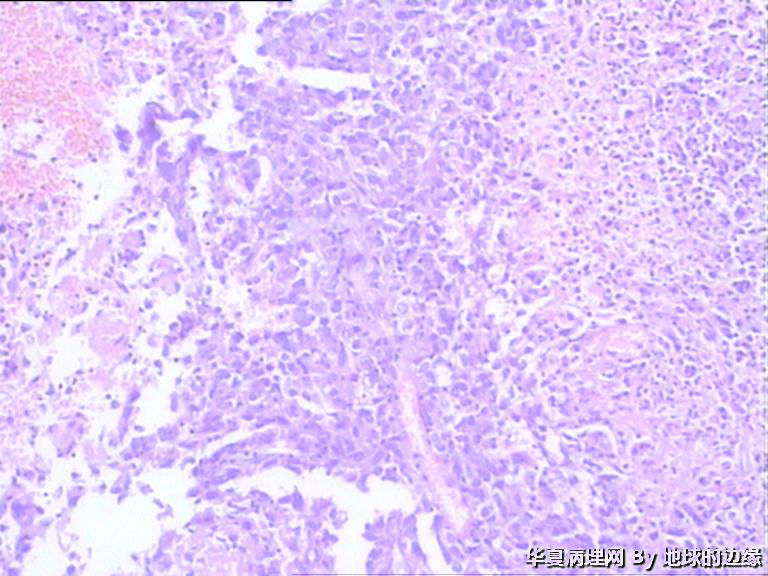

右肱骨肿瘤待查

病人女性,48岁

MRI示:右肱骨肿瘤待排,包块大小为10x8cm,活动度差,边界欠清,鱼肉组织(白色),肿块侵犯至骨外    组  织。

目前Vimentin阳性,P53阳性,AFP,EMA,CK7,CK20,E-ca,CR,PLAP,CD99,ER,PR,CEA,均阴性,只是没做淋巴瘤这一套了